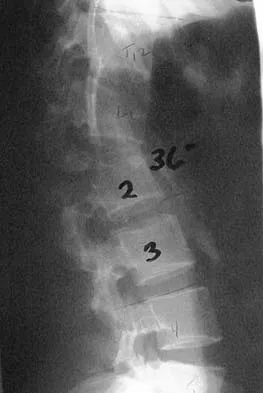

Question 77High Yield

An otherwise healthy 70-year-old man has back and bilateral leg pain in an L5 distribution that is aggravated by standing more than 10 minutes or walking more than 100 feet. He has to sit to get relief. Neurologic and pulse examinations are normal. A radiograph and MRI scan are shown in Figures 4a and 4b. Treatment should consist of

Explanation

The patient has a degenerative spondylolisthesis at L4-5 with associated spinal stenosis. His symptoms are consistent with neurogenic claudication. Based on these findings, the surgical treatment of choice is decompression and posterolateral fusion. Use of instrumentation is controversial. Laminectomy alone is reserved for the patient who is frail medically. There is no role for an anterior approach or for fusion alone without decompression. Fischgrund JS, Mackay M, Herkowitz HN, et al: Degenerative lumbar spondylolisthesis with spinal stenosis: A prospective, randomized study comparing decompressive laminectomy and arthrodesis with and without spinal instrumentation. Spine 1997;22:2807-2812.